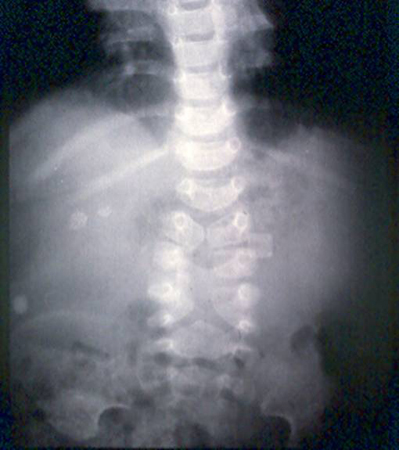

Abdominal x-ray demonstrating double bubble gas pattern consistent with duodenal atresia

From the collection of Dr KuoJen Tsao; used with permission